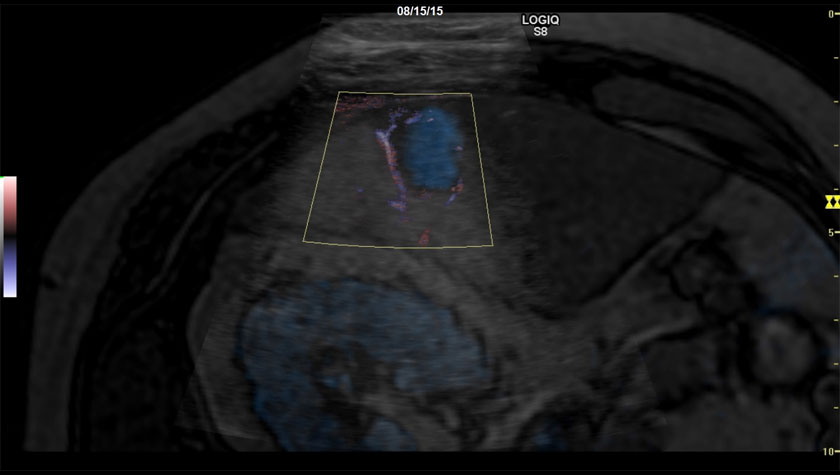

Объемная навигация + цветовой B-Flow, датчик C1-5-D

Сосудистая сеть шейного лимфоузла, УЗИ с контрастами (CEUS) + B-FLOW, датчик 9L-D

- Coded Contrast Imaging — Опция для исследования с контрастными веществами;

- Режим B-flow – оценивает гемодинамику во всех типах сосудов: от крупных кровеносных сосудов, например, сонной артерии, до мелких сосудов паренхиматозных органов.